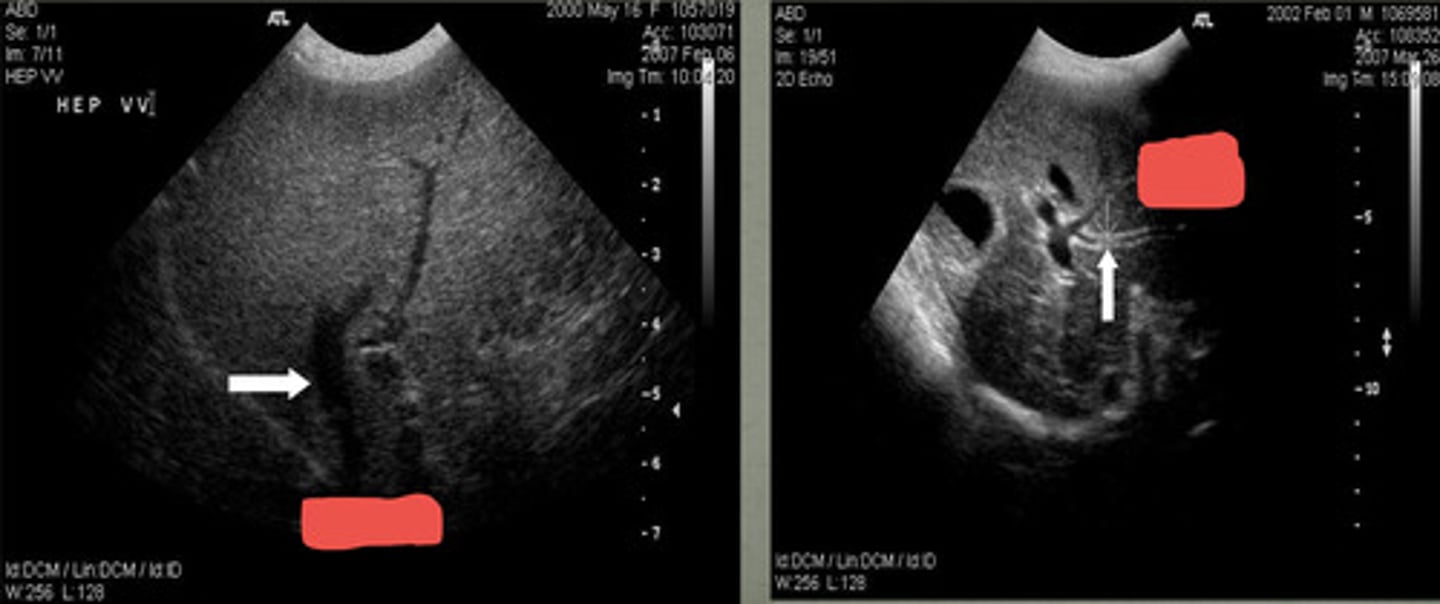

portal veins

the _____ veins have the most echogenic walls

at the diaphragm

hepatic veins join the caudal vena cava where?

anechoic

the hepatic veins are what echogenicity?

hepatic veins

do portal veins or hepatic veins have less delineated walls?

hyperechoic

portal veins have a more _______ border than the hepatic veins

left- hepatic vein

right- portal vein

which US shows the portal vein and which is hepatic vein?

hepatic

______ arteries are not detected on 2D images and only found with color flow Doppler

arteries

with color doppler, _______ are the small vascular structures depicted with red color